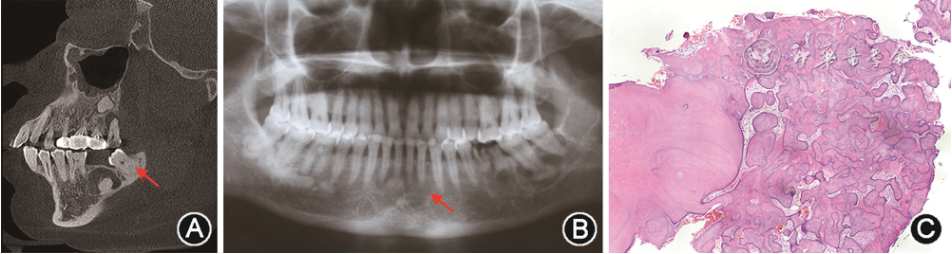

根据影像学特点,FocCOD病变可分为早、中、晚期3个阶段,早期病变表现为下颌牙根尖部界限清楚的放射透光区;中期表现为放射性透光区与放射性阻射区混合影,或在阻射区周围有界限清楚的透射环(图1A);晚期表现为弥散性放射性阻射影,通常边界不清。光镜下可见粗大曲线形骨小梁或不规则形牙骨质样团块,周围少见成骨细胞。

图1 牙骨质-骨结构不良(COD)的影像学和病理学表现 A:局灶性COD的CT片显示阻射区周围有界限清楚的透射环(箭头示);B:繁茂性COD的曲面体层X线片显示累及下颌骨双侧的透射阻射混合影(箭头示);C:繁茂性COD的病理学表现显示不规则骨样团块(HE染色 低倍放大)

(3)FCOD:FCOD可累及颌骨两个及以上象限[12],大部分病例累及下颌骨双侧、累及或不累及上颌骨,常在下颌骨磨牙或前磨牙区。患者发病年龄多为47~49岁,黑人女性较多见[8]。FCOD通常无症状,呈对称性分布,部分病例可发生囊性变及颌骨膨隆[11]。FCOD的X线及病理特征与FocCOD相似(图1B,C)。当X线表现为不规则或多房性放射性透光区时,类似于单纯性骨囊肿,但无囊肿的上皮衬里。